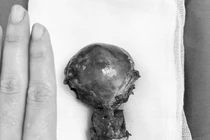

Trước diễn biến bệnh phức tạp, bệnh nhân được truyền 05 đơn vị hồng cầu và được nội soi đặt sonde JJ niệu quản 2 bên, sau đó mổ mở cắt tử cung hoàn toàn và hai buồng trứng. Kíp phẫu thuật do BSCKI Nguyễn Văn Mạnh, Phó trưởng khoa Phụ sản và ê kíp đã thực hiện thành công lấy ra khối u nặng 3,5kg sau gần 2 giờ.

Khối u nặng 3,5kg được cắt bỏ - Ảnh BVCC